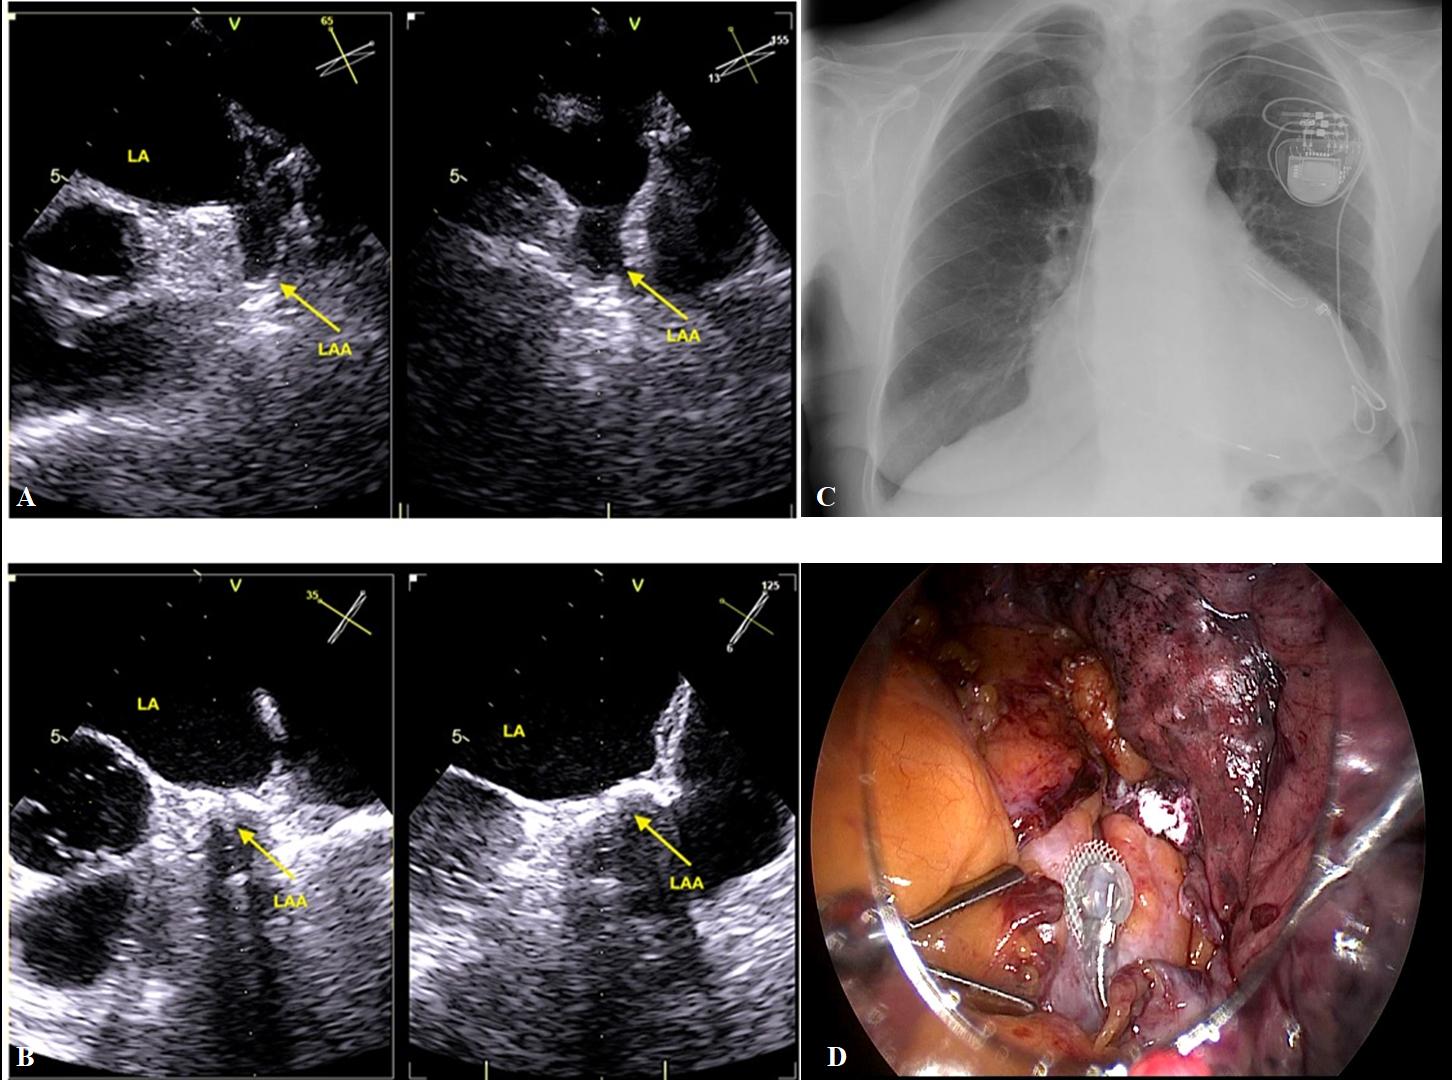

This procedure can be performed successful concomitant procedure as TT epicardial left ventricular lead implantation for cardiac pacemaker/implantable automatic defibrillator cardiac resynchronization device also [69] (Fig. 4).

Fig. 4.A case of TT concomitant LAA exclusion closure and left ventricular epicardial lead implantation. (A,B) Describes TEE monitoring before and after TT LAA exclusion with AtriClip device. (C) Describes antero-posterior chest x-ray image after LAA exclusion and epicardial LV implantation. (D) Highlights image of LAA exclusion and epicardial left ventricular epicardial lead before left lung was re-expansion.